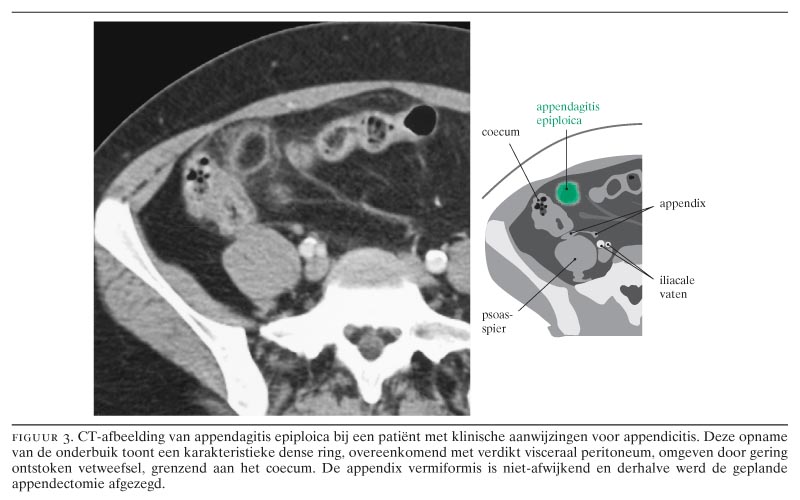

De karakteristieke echografische bevinding bij appendagitis epiploica is een 1 tot 4 cm grote intra-abdominaal gelokaliseerde massa van echorijk ontstoken vetweefsel, dat vastzit aan het colon, exact op de plek van de meeste pijnklachten (figuur 2).5 9 Met CT bevestigt men de diagnose door het aantonen van een karakteristieke dense ring in of rondom het ontstoken vetweefsel (figuur 3), hetgeen overeenkomt met oedemateus verdikt visceraal peritoneum rondom de ontstoken appendix epiploica.5 6 9

De klinische waarschijnlijkheidsdiagnose voordat echografie en CT werd verricht, luidde ‘sigmoïddiverticulitis’ bij 32 patiënten (65), ‘appendicitis’ bij 10 patiënten (20), ‘cholecystitis’ bij 2 patiënten (4), ‘salpingitis’ bij 2 patiënten (4), ‘appendagitis epiploica’ bij 2 patiënten (4) en ‘nefrolithiasis’ bij 1 patiënt (2).